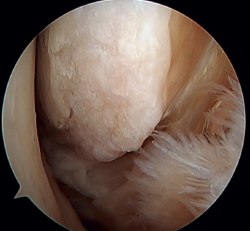

Arthroscopic treatment of rotational/multidirectional instability

Rotational instability is a relatively novel concept introduced in 2011 by Buchhorn(67), describing combined injuries of the lateral complex and deltoid ligament, and an anatomical reconstruction technique for both injuries. Although there is no biomechanical evidence as to why medial injury occurs in patients who have not suffered eversion trauma, it is likely that the stress maintained on the medial complex in lateral instability may evolve into rotational instability - which is in line with the previously commented domino effect theory (5,62). It is estimated that up to 10-15% of all cases of CLAI may progress to injury of the medial complex, especially affecting its most anterior fibers. Recently, Vega(68) described the combination of injuries of the lateral complex with the "book-page" injury (Figure 7) of the superficial tibiotalar fascicle of the deltoid ligament, due to excessive internal rotation in chronic lateral instability, and its treatment through direct repair of both lesions. Acevedo(34) and Vega(68) also described the safety position of the anchors in the medial malleolus.